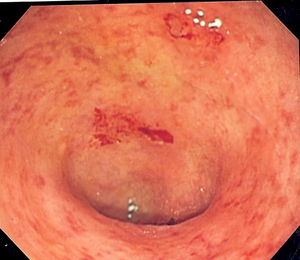

| Endoscopic image of a sigmoid colon afflicted with ulcerative colitis. Note the vascular pattern of the colon granularity and focal friability of the mucosa. | |